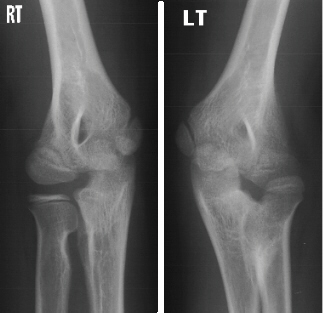

Order of Xray links: 1. Internal Rotation, 2. External Rotation,

3. AP, 4. Lateral.

The patient is an 11 year old, otherwise completely healthy

boy, who presented for evaluation of his left arm. He states he

has always had limited range of motion of his left arm, however,

his mother states that it was not until recently she became concerned.

The patient is right hand dominant. This does not cause him any

functional problems and he has no pain. The mother and boy are

concerned because the right and left arms are different. The left

arm demonstrates a shoulder with full range of motion (ROM) and

strength 5/5. The elbow has a flexion from 0 to 135 degrees, but

the forearm is fixed in 45 degrees of pronation without active

or passive supination. The wrist has full ROM with some hyper-mobility,

especially in radial and ulnar deviation. The strength is 5/5

in elbow flexion/extension, wrist flexion/extension and grip.

He is neurovascularly, intact. The right arm also demonstrates

normal motion at the elbow with flexion from 0-135 degrees but

limited supination from 0-50 degrees and pronation from 0-20 degrees.

The remainder of his exam was normal.

right arm is normal and the left arm has radioulnar synostois.